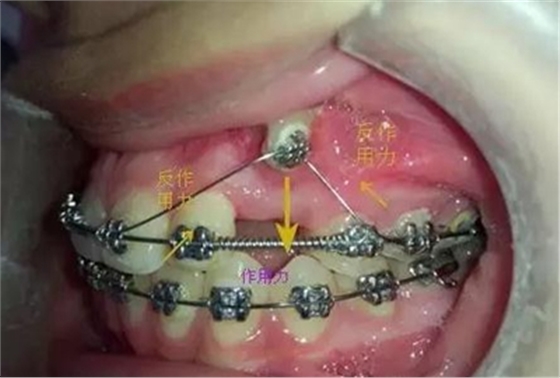

考慮到如果能像種植支抗,水平方向或者向唇側(cè)牽引移動,可以有效避免垂直方向牽引力壓迫側(cè)切牙根尖部,所以我和病人溝通了一下,建議采用種植支抗,但是病人不想增加費用。

那好吧還是采用輔弓增加支抗,經(jīng)濟適用,也便與操作,0.8不銹鋼絲彎制,進行熱處理,增加其彈力。

當尖牙到達了指定位置后,又采用了主弓絲和附弓絲,主弓絲采用了不銹鋼絲方絲,有效的避免了反作用力引起相鄰的牙齒出現(xiàn)小開合, 維護牙弓形態(tài)。

主弓絲和輔弓絲的結(jié)合使用,可以有效避免出現(xiàn)小開合,同志們一定要注意啊!